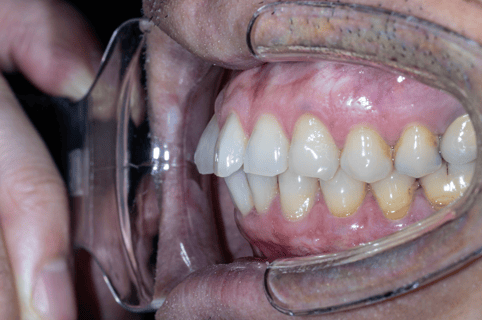

- 齒列排列不整,牙弓偏窄

- 咬合接觸不均,後牙支撐不足

- 下顎位置偏後,口咽空間受限